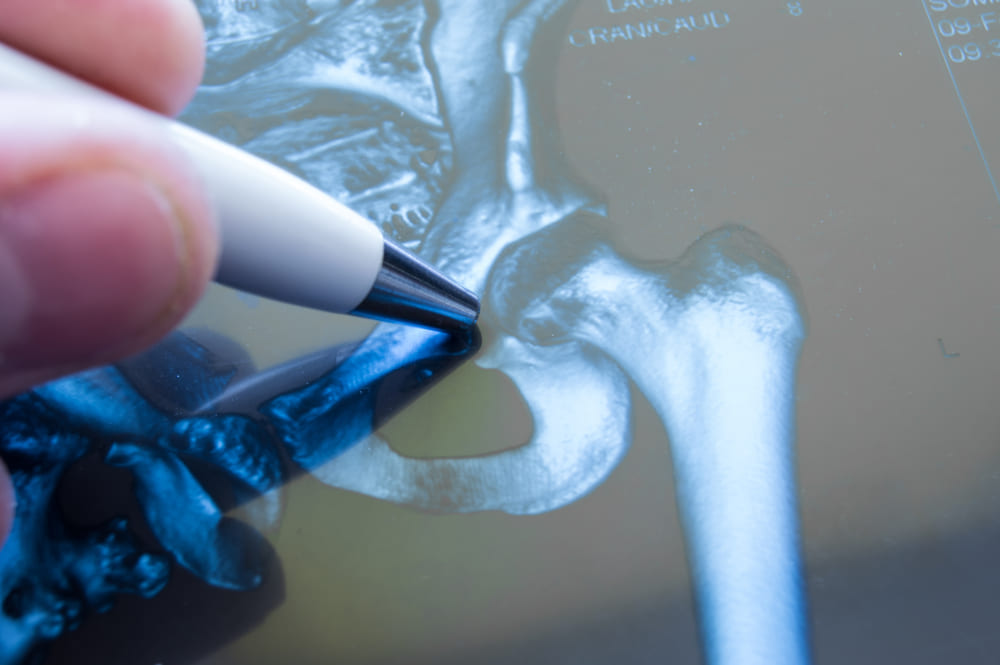

- рентген (проводится всегда, но на ранних стадиях часто не дает полного представления о характере патологического состояния);

- компьютерная томография, во много раз более точный метод лучевой диагностики, помогает определить заболевание даже на самой ранней стадии, когда симптомов расстройства еще нет;

- сцинтиграфия, определение характера изменений возможно по распределению радиоизотопного препарата, можно обнаружить патологический процесс еще на стадии нарушений кровотока, когда расстройство только-только развивается.